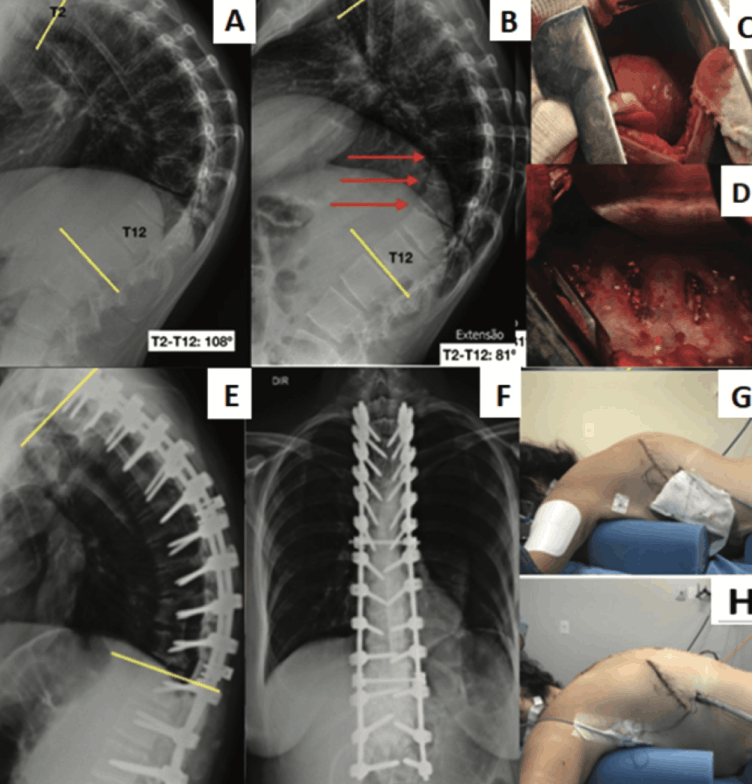

Scheuermann's Kyphosis: Case Series and Literature Review.

Por Dr. Chrystiano Fonseca Cardoso.

Scheuermann's Kyphosis (SK) is a spinal deformity characterized by abnormal curvature in the thoracic region, with vertebral bodies having a wedge-shaped appearance, with the posterior portion being taller than the anterior part. This condition may result in chronic pain, aesthetic changes, and, in severe cases, significant functional restrictions. Early diagnosis and appropriate treatment are crucial to prevent the progression of deformity and minimize long-term complications [1,2].

The prevalence of SK in the general population is estimated to be between 0.4% and8%,mostcommonlyaffectingadolescents during growth. Although the exact cause of the disease is unknown, genetic and biomechanical factors are believed to play an important role in its development [3,4]. The therapeutic approach is varied and depends on the severity of the deformity, the patient's age, and the symptoms presented [2,5].